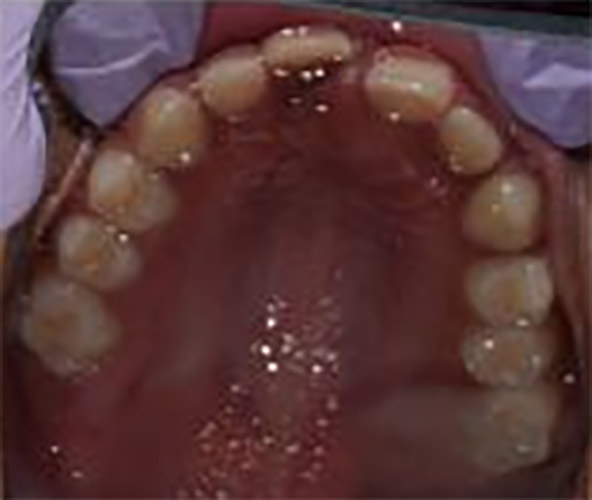

Pre Tx Diagnostic Models

Figures 7 & 8 diagnostic models from first visit